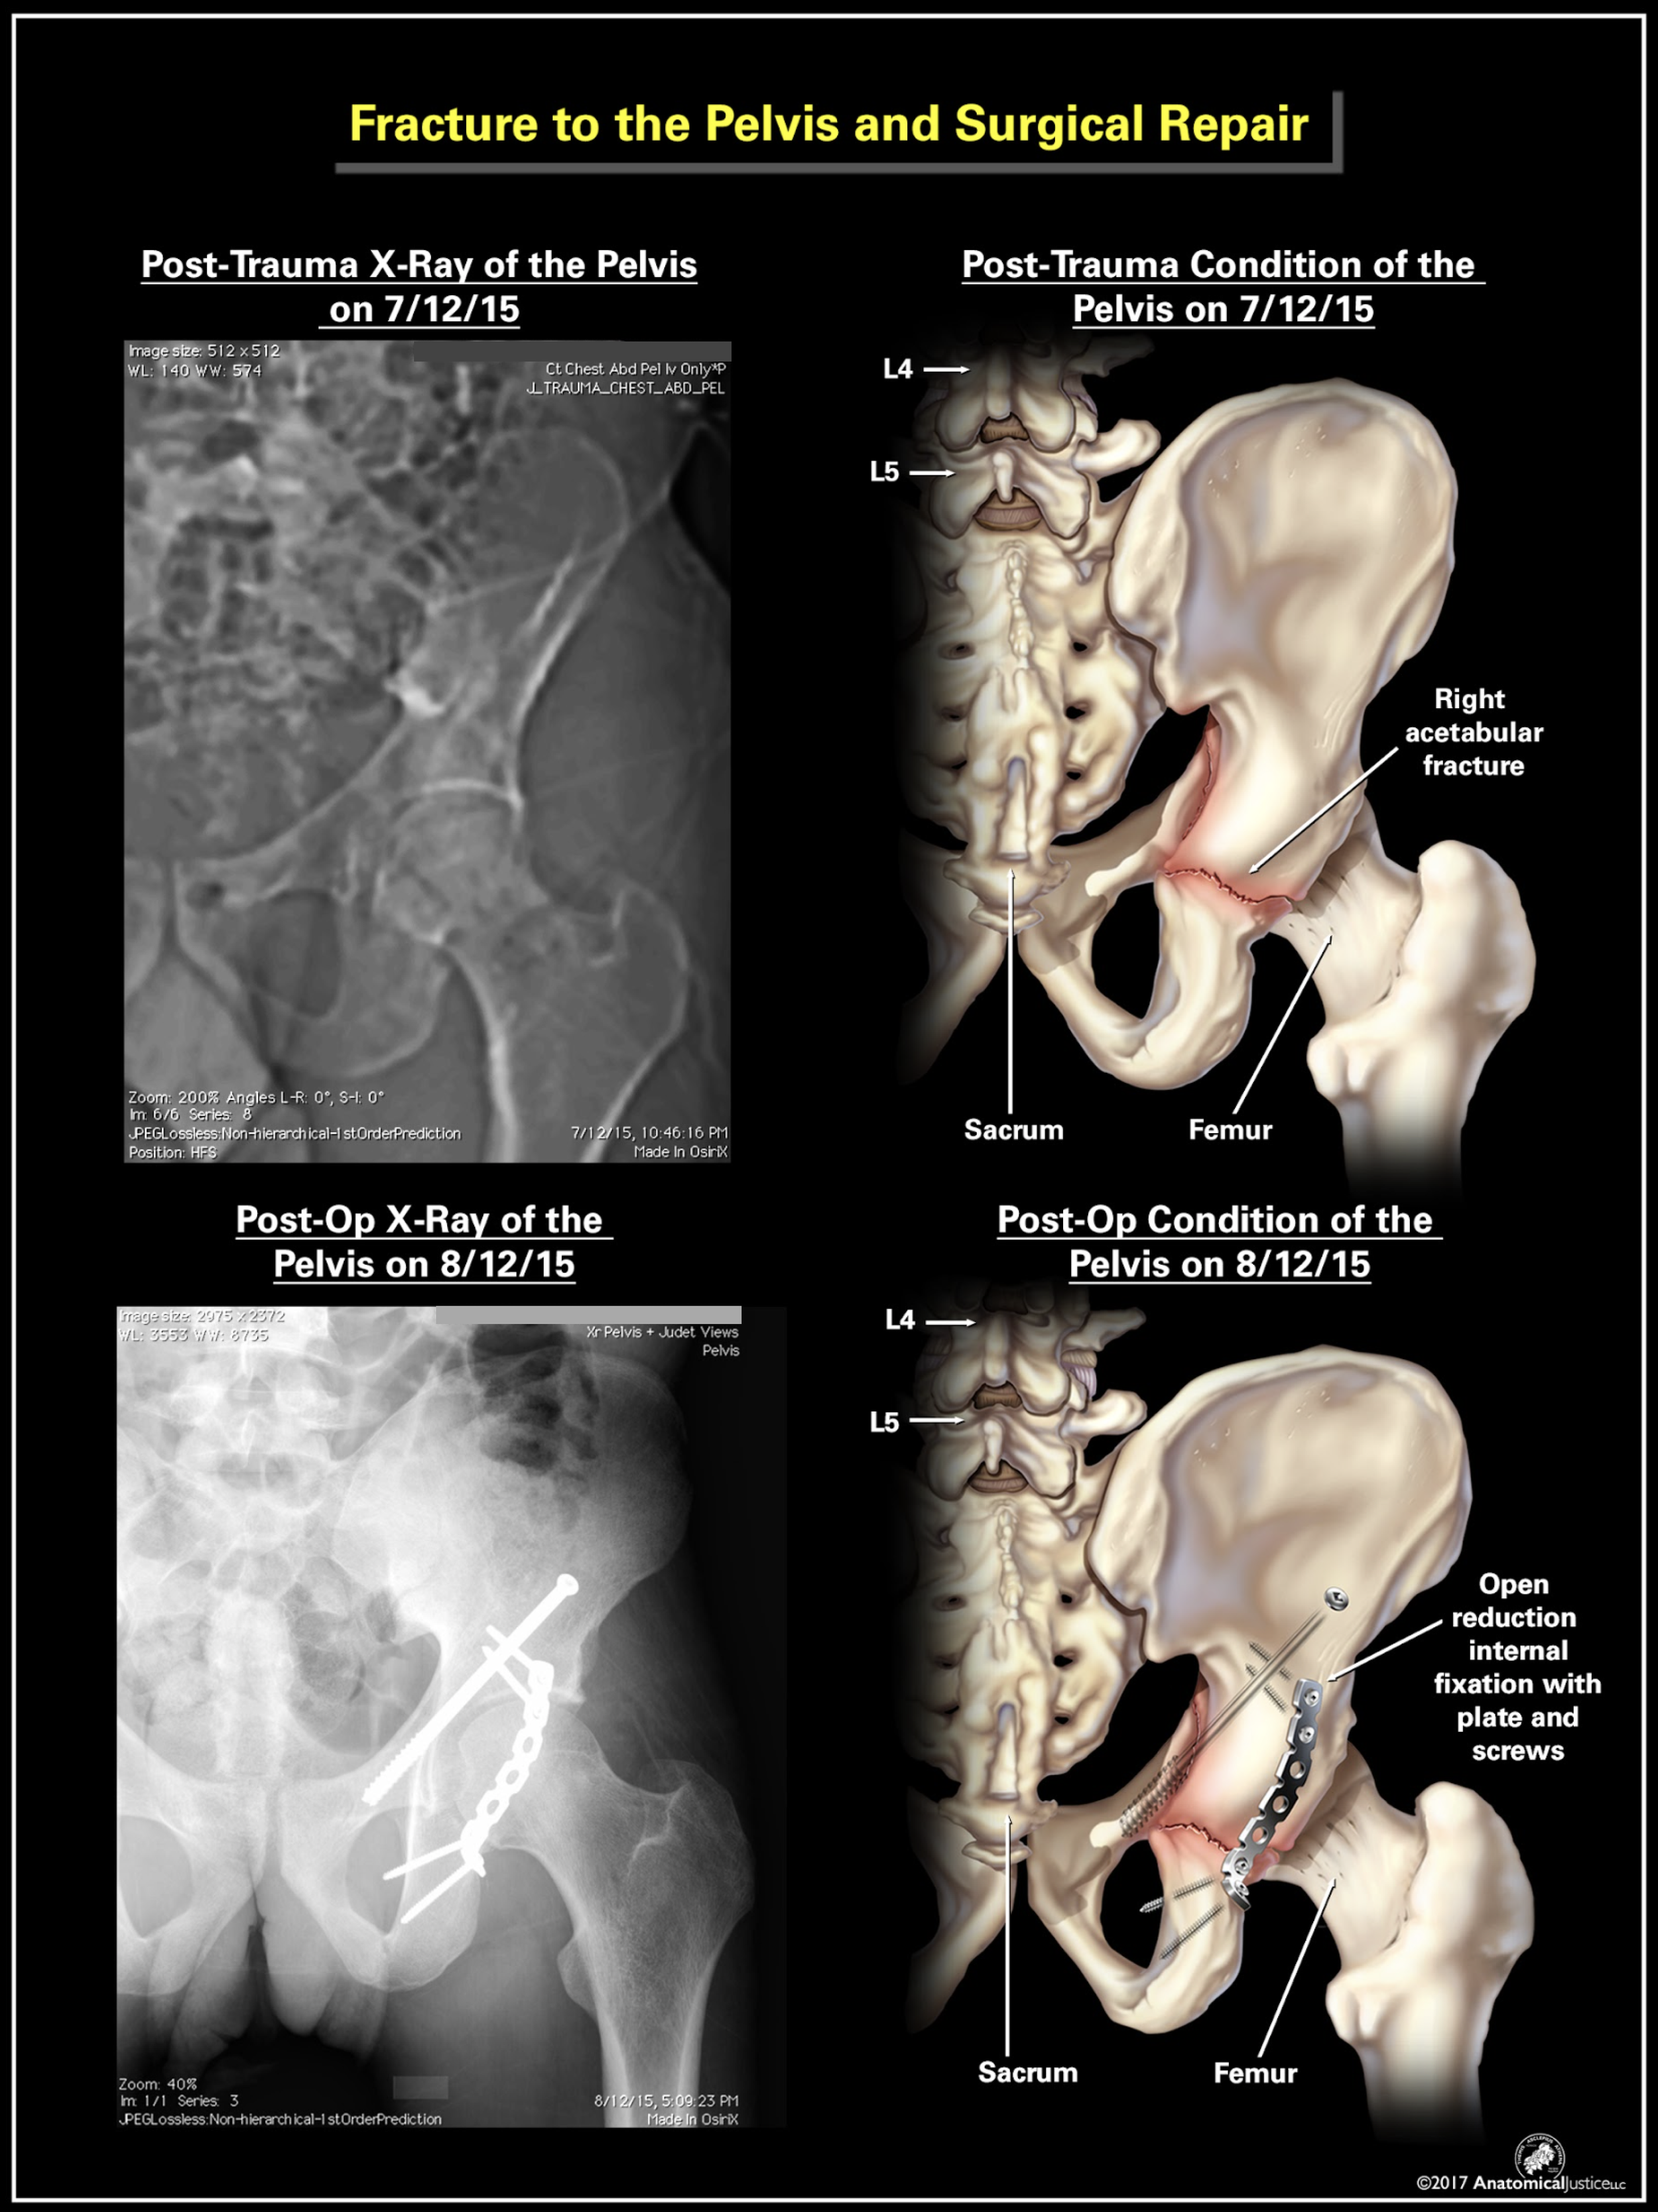

Digitally illustrated in Adobe Photoshop for Anatomical Justice. This piece was utilized in a legal case, with all names and personal information removed. Copyright belongs to Anatomical Justice, LLC; all rights reserved.

Digitally illustrated in Adobe Photoshop for Anatomical Justice. This piece was utilized in a legal case, with all names and personal information removed. Copyright belongs to Anatomical Justice, LLC; all rights reserved.